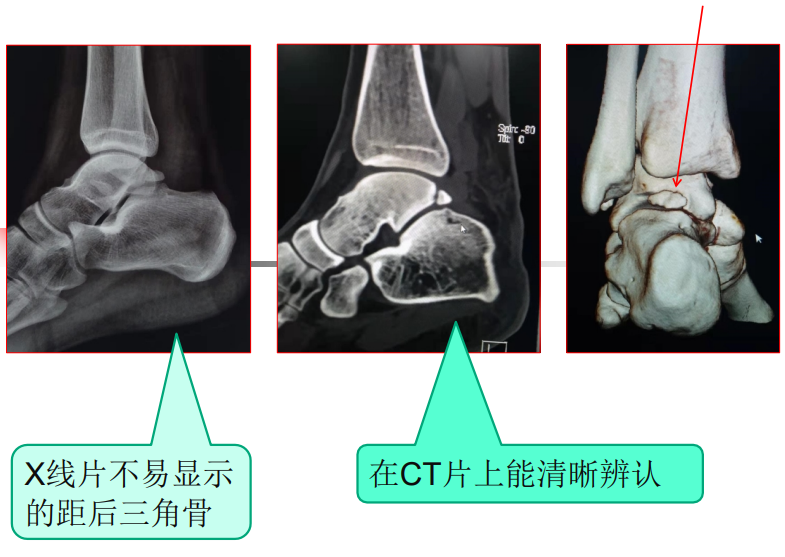

踝关节后方疼痛,当心距后三角骨损伤找上门!

1840年Rosenmuller首先描述了 距后三角骨的存在。

距后三角骨总的发生率在1.7--7%

在青春期前(男性11岁--13岁,女性8--10岁),距骨后内侧结节和后外侧结节出现第二骨化中心,并在一 年内与距骨体融合。